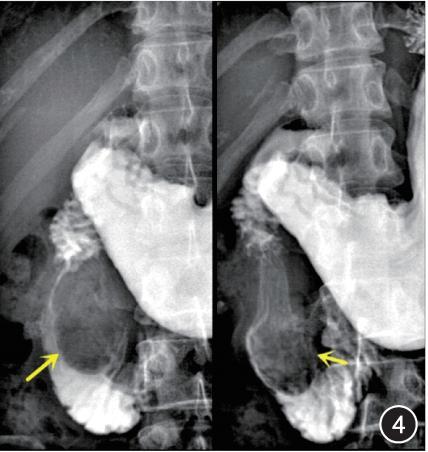

十二指肠镜:十二指肠降部内侧壁可见黏膜下隆起病变,隆起病变的右侧可见十二指肠乳头,乳头开口未见异常(图3)。上消化道造影:十二指肠降部卵圆形压迹,大小约58 mm×34 mm,边界光滑,形态不固定,随肠管蠕动有变化,未见造影剂进入囊腔(图4)。

图4 上消化道造影见十二指肠降部卵圆形压迹(黄色箭头所示),形态不固定、随肠管蠕动有变化,未见造影剂进入囊腔